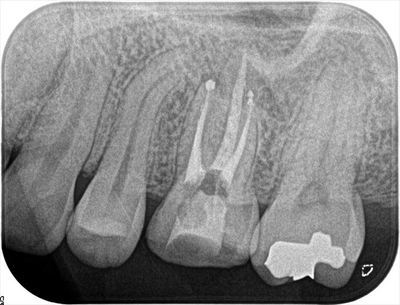

レントゲン画像です。(矢印部分が左上第一大臼歯)

過去に神経の処置をしてある失活歯です。

垂直加圧根管充填を行ったあとのデンタルX線画像です。